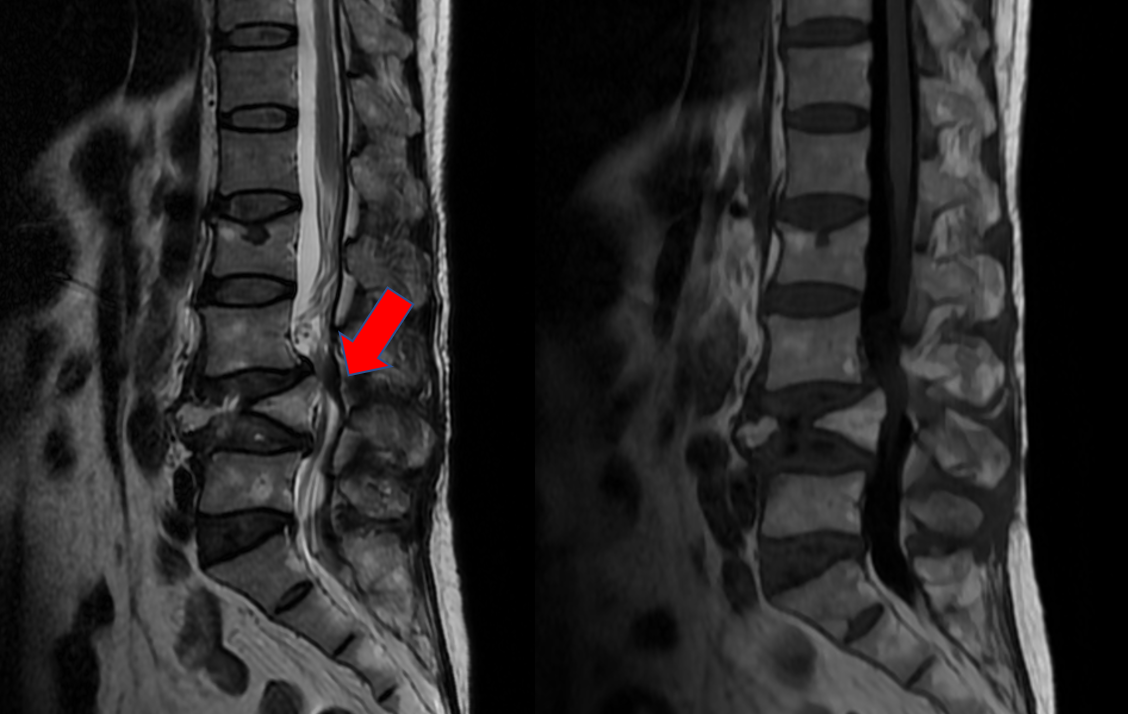

L4椎体陈旧性骨折,椎体高度塌陷严重

患者L4椎体几乎完全压缩,骨块已突入椎管,椎管严重狭窄

L4水平椎管狭窄明显,造成患者双下肢乏力、麻木